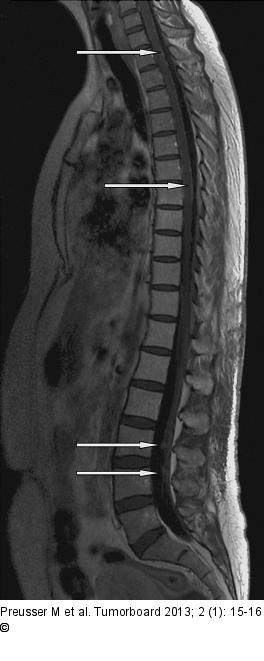

Abbildung 1: Meningeosis carcinomatosa Sagittale T1-gewichtete Sequenz der BWS und LWS. Teils noduläre, teils plaqueartig der Myelonoberfläche anliegende, kontrastmittelaufnehmende Läsionen im Sinne einer ausgedehnten leptomeningealen Metastasierung im Rahmen der Grunderkrankung |

Abbildung 1: Meningeosis carcinomatosa

Sagittale T1-gewichtete Sequenz der BWS und LWS. Teils noduläre, teils plaqueartig der Myelonoberfläche anliegende, kontrastmittelaufnehmende Läsionen im Sinne einer ausgedehnten leptomeningealen Metastasierung im Rahmen der Grunderkrankung |